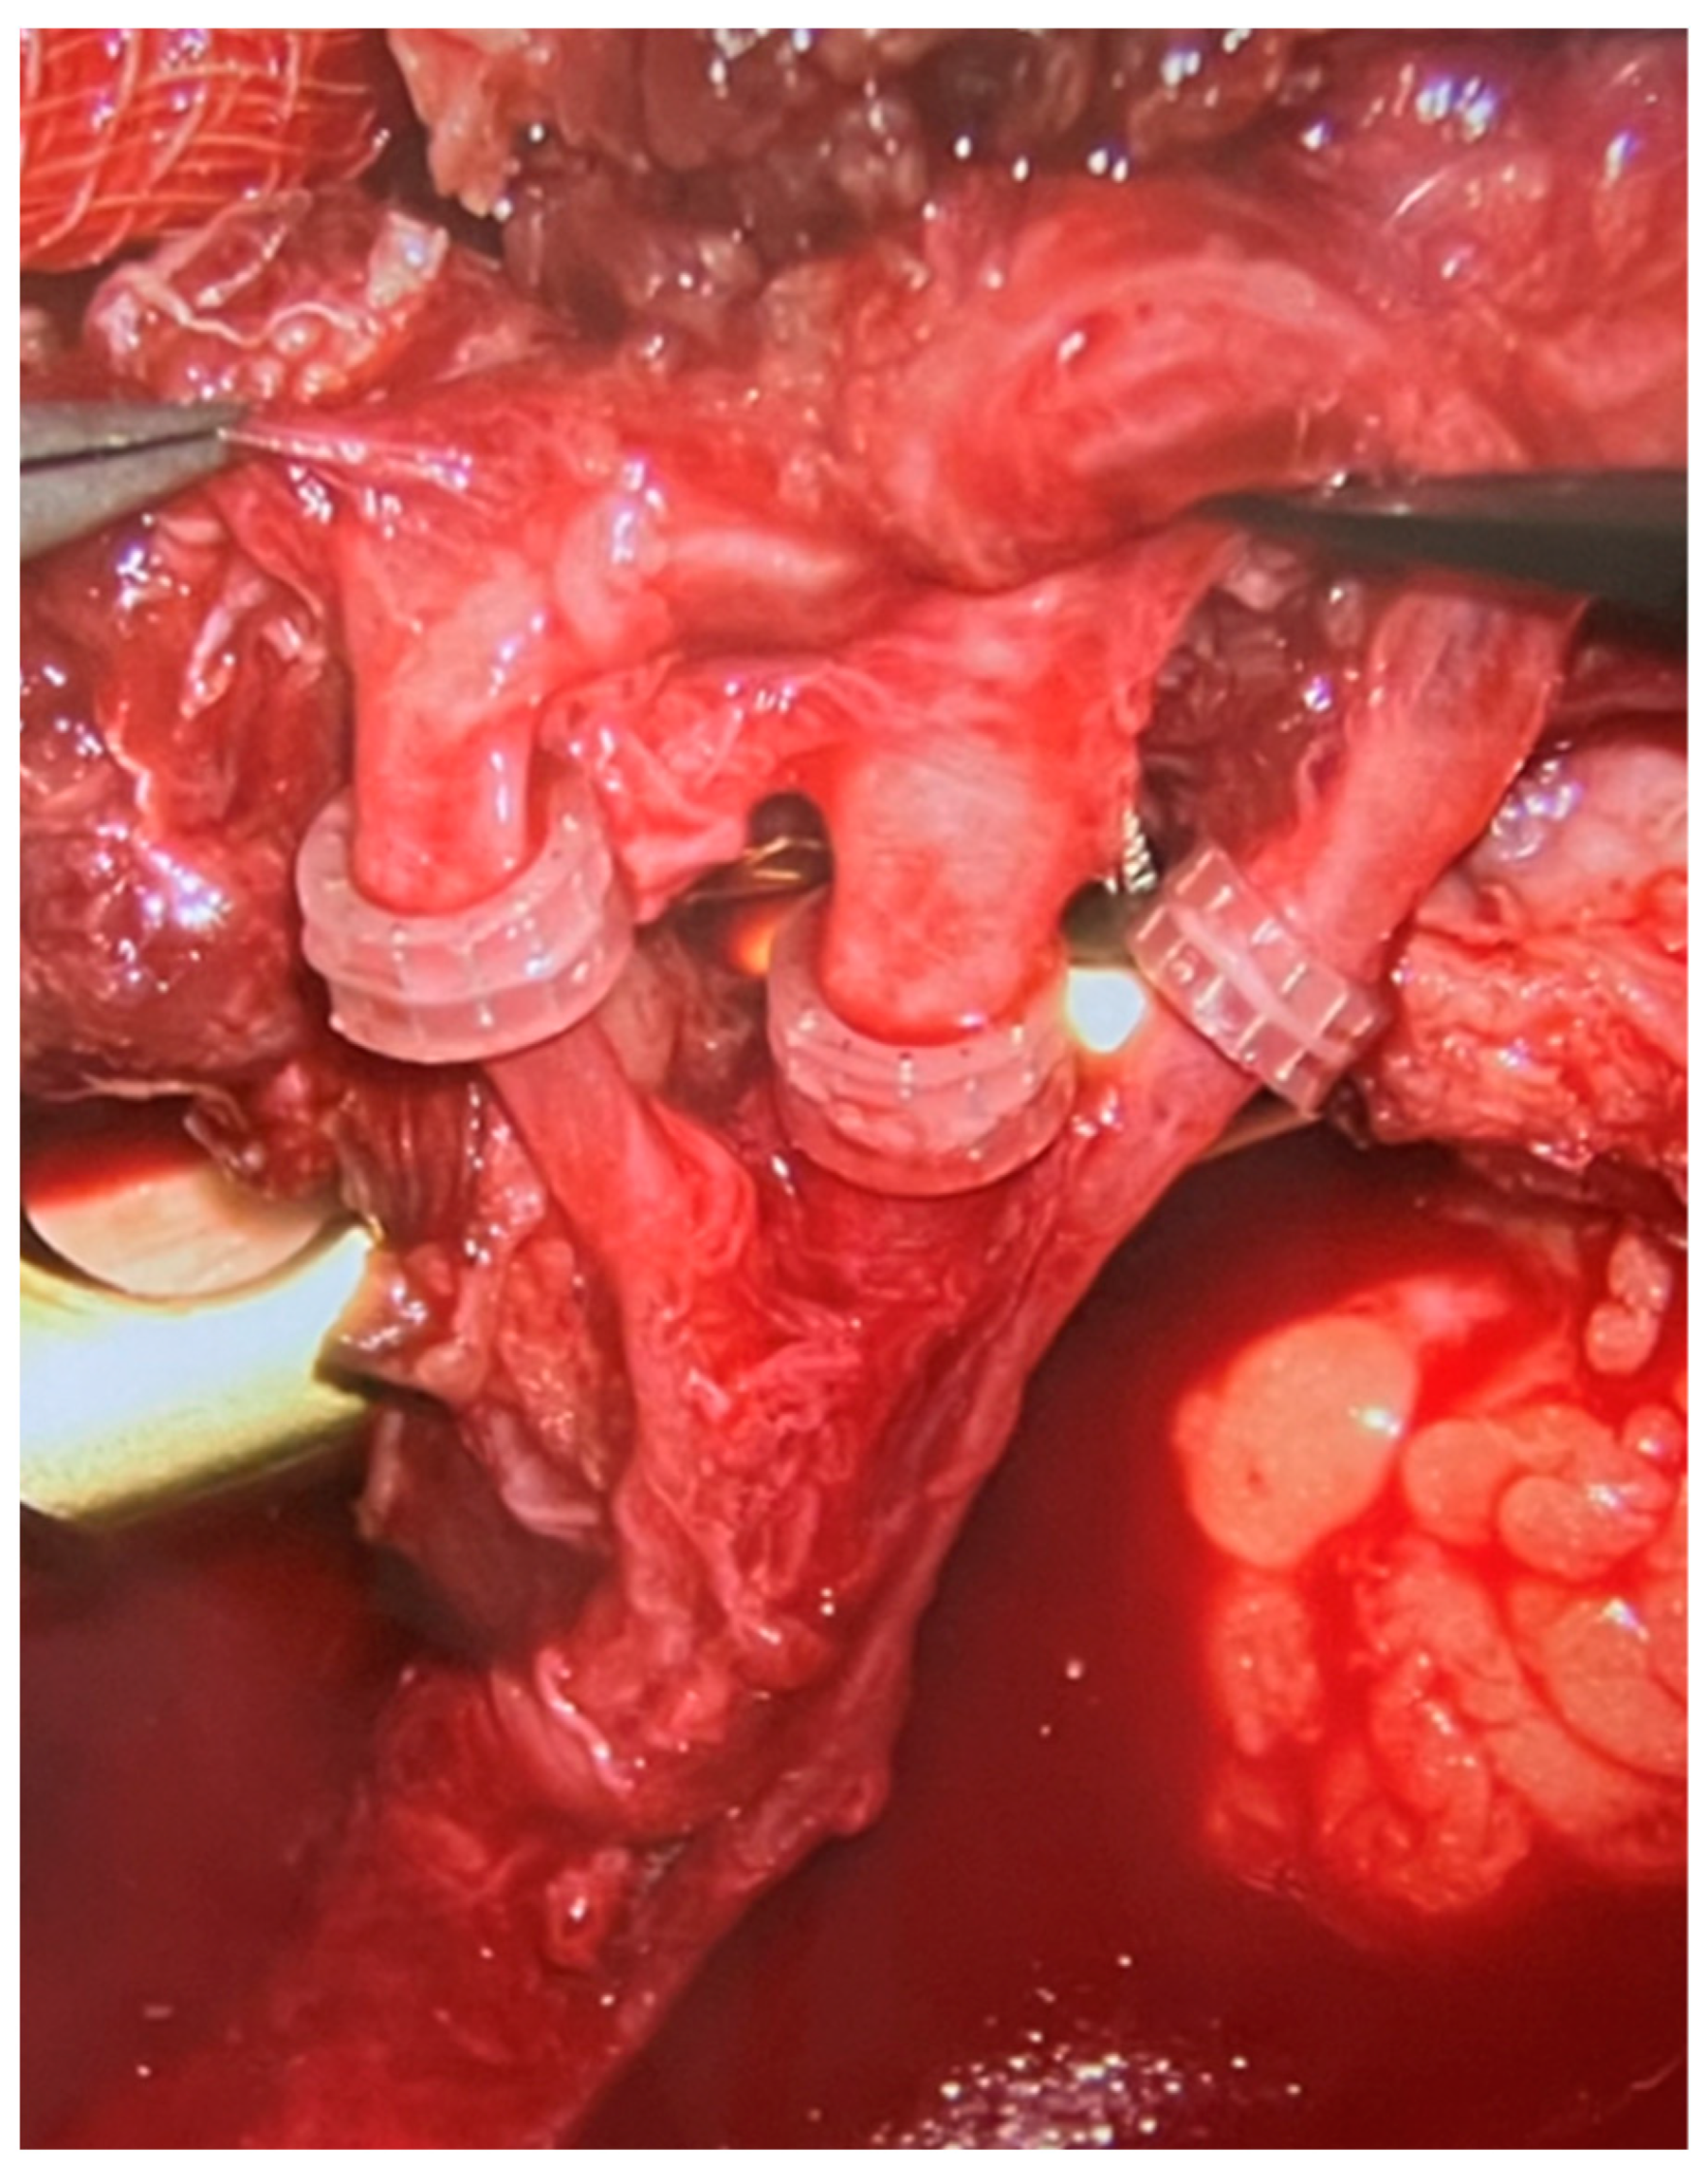

The microvascular anastomoses were performed according to the available local vessels. Most commonly, the anastomoses were performed in end-to-end fashion to anterior tibial vessels. What needs to be emphasized is that in every case we performed two venous anastomoses—one to the deep venous system and one to the superficial venous system (most commonly the saphenous vein). Almost all arterial anastomoses were hand sewn using 9–0 or 10–0 nylon sutures. On the other hand, all veins were anastomosed using the microvascular anastomotic coupler system, as presented in the Figure 6 (Synovis Micro Companies Alliance, Birmingham, AL, USA). The average size of coupler used was 2.5 mm (range 1.5–4 millimeters).

In microsurgery, the most common perioperative complication requiring urgent surgical intervention and frequently leading to partial tissue necrosis of the free flap is venous insufficiency, most commonly resulting from obstruction of the venous anastomosis [18]. Venous insufficiency is a much more common complication compared to arterial insufficiency regarding the free flaps. For this reason, in patients treated at the Institute of Mother and Child, in order to minimize the risk of the most common cause of flap perfusion impairment, two microsurgical venous anastomoses were performed during each procedure (Figure 6). One of them was performed in the deep venous system, the other in the superficial venous system.

Figure 6. Intraoperative photograph from a surgical microscope. Three microvascular anastomoses are visible—one arterial (in the middle) and two venous (on the sides), all performed with the use of a coupler device.